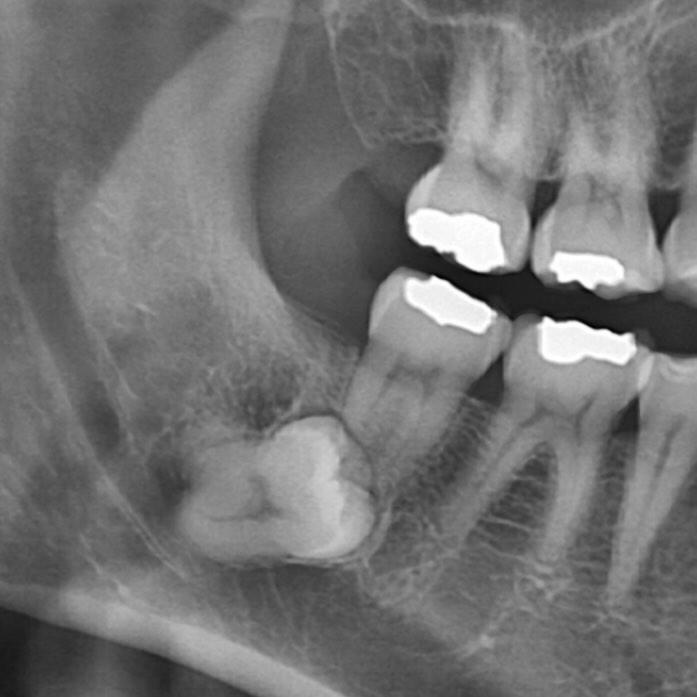

이 정도면 사랑니 발치 고난도라고 합니다. 문외한인 제가 봐도 왠지 움찔하게 되네요...;;